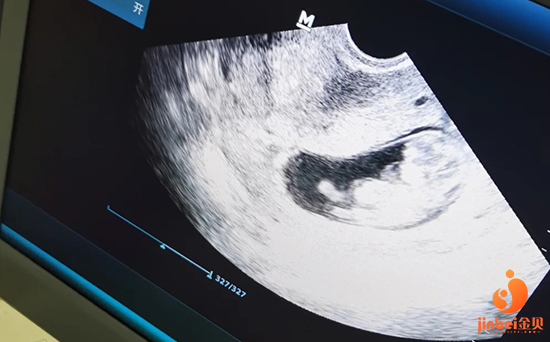

预测排卵:主要是B超监测卵泡的发育程度,以确定给予激素诱发排卵的最佳时间。

采集卵子:于卵泡发育成熟尚未破裂时,在腹腔镜下经腹或在B超监视下,经阴道以针穿刺成熟卵泡,抽取卵泡内容物,找出卵母细胞。

预测排卵:要取排卵前成熟的卵子,首先要确定排卵期。主要是B超监测卵泡的发育程度,以确定给予激素诱发排卵的最佳时间。